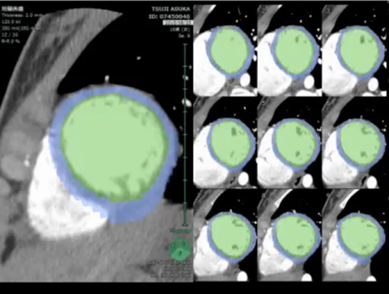

On physical examination, the patient’s heart rate was 70 beats per minute and her blood pressure was 107/58 mmHg (systolic/diastolic). Her height was 152.3 cm, her weight was 44.6 kg, and her body mass index was 19.2. Cardiac examination revealed normal S1 and S2 and no discernible murmur. No apparent abnormalities were detected on X-ray and laboratory testing (including B-type natriuretic peptide, human atrial natriuretic peptide, troponin-I, HbA1c, triglycerides, cholesterol, renin-angiotensin system, and catecholamine). ECG showed subtle ST depression (<0.1 mV) in inferior leads (II, III, and aVF) and subtle ST elevation (0.2 mV at maximum) in the anteroseptal leads (V1–3). The T-wave was inverted in lead III and flattened in lead aVF (Fig. 1). Transthoracic echocardiography showed no abnormalities. A treadmill exercise ECG test was performed according to the standard Bruce protocol. During stage 5, chest pain was induced and the ECG showed nonspecific upsloping ST depression in the inferior leads (II, III, and aVF) and subtle ST elevation in the anteroseptal leads (V1–3; Fig. 2). ECG alterations disappeared after a few minutes’ rest, but chest pain persisted for approximately 15 minutes and was not alleviated by nitroglycerin treatment. Exercise thallium-201 myocardial scintigraphy showed perfusion defects in the anteroseptal wall, which improved during the resting study in the peripheral regions, but not in the central areas. The minimal concentration of tracer in the perfusion defects was 55% of that in normal regions (Fig. 3A, B). Resting thallium-201 myocardial scintigraphy and 123I-BMIPP scintigraphy were performed on different days, and both revealed perfusion defects in the anteroseptal wall, with observed perfusion defects being greater on 123I-BMIPP scintigraphy (Fig. 3C, D). Left ventricular function was evaluated with echocardiography during intravenous adrenaline infusion (0.1 µg/kg/min after 0.1 mg/kg bolus administration). Chest pain was induced shortly after adrenaline infusion, and reduced regional systolic wall thickening was noted in the anteroseptal wall. A cardiac computed tomography (CT) scan showed no abnormalities of the coronary arteries. However, 4D-CT revealed hypokinesia and thinning of the anteroseptal wall (Video 1). During coronary angiography, the patient complained of chest discomfort when the venous catheter was moved within the right atrium, but no significant stenosis was observed in the epicardial coronary arteries. An ergonovine spasm stimulation test induced chest pain, and ergonovine infusion into the left coronary artery was followed by significant ST depression in the inferior leads (II, III, and aVF) and ST elevation in the anteroseptal leads (V2–4). Coronary spasm was not induced, but delayed distal vessel opacification was noted in the left anterior descending (LAD) artery (Video 2). After a few minutes, ECG alterations and delayed distal vessel opacification disappeared spontaneously, although the chest pain persisted for a few hours.

Fig. 3 Exercise thallium-201 myocardial scintigraphy shows perfusion defect in the anteroseptal wall during exercise (A), which persists after a period of rest (B). Resting thallium-201 scintigraphy (C) and 123I-BMIPP scintigraphy (D) also demonstrated a perfusion defect in the anteroseptal wall

The patient was diagnosed with microvascular angina on the basis of myocardial scintigraphy, which indicated myocardial ischemia despite the absence of stenosis or spasm of epicardial coronary arteries. Atenolol (50 mg once daily) was administered, but failed to alleviate the symptoms, and chest pain was experienced more frequently during the winter. After 4 months, thallium-201 myocardial scintigraphy showed exacerbation of ischemia in the anteroseptal wall (Fig. 4). Therefore, medication was changed to carvedilol (10 mg twice a day) and exercise was prohibited. However, chest pain did not improve, and 2 months later, diltiazem treatment (100 mg, once daily) was introduced to the ongoing carvedilol regimen. The patient’s symptoms gradually improved, and 3 months later, thallium-201 myocardial scintigraphy showed a reduced ischemic area (Fig. 4).

Fig. 4 The perfusion defect of exercise thallium-201 myocardial scintigraphy deteriorated despite treatment with atenolol (A). Concomitant use of carvedilol and diltiazem in addition to exercise limitation reduced the frequency of chest pain. The perfusion defect of exercise scintigraphy was also improved (B)

The scintigraphy results in this patient were distinctive, being round in shape, and although the scintigraphy suggested significant cardiac ischemia, there were few abnormalities in the ECG, ultrasonography, and 4D-CT. We believe that these findings suggest that myocardial ischemia developed without regard to the distribution of epicardial coronary arteries, and ischemic and normal myocardia existed in a mosaic pattern in the cardiac muscle layer, as is consistent with the characteristics of microvascular angina.3) However, some findings, such as the ST elevation at ECG and persistent perfusion defects at the scintigraphy, are not typical of microvascular angina. Coronary microvascular dysfunction develops in other diseases, such as cardiomyopathy.4) In our case, cardiomyopathy was ruled out on the basis of current diagnostic criteria, but we consider that follow-up should be conducted to monitor the possible development of cardiomyopathy.